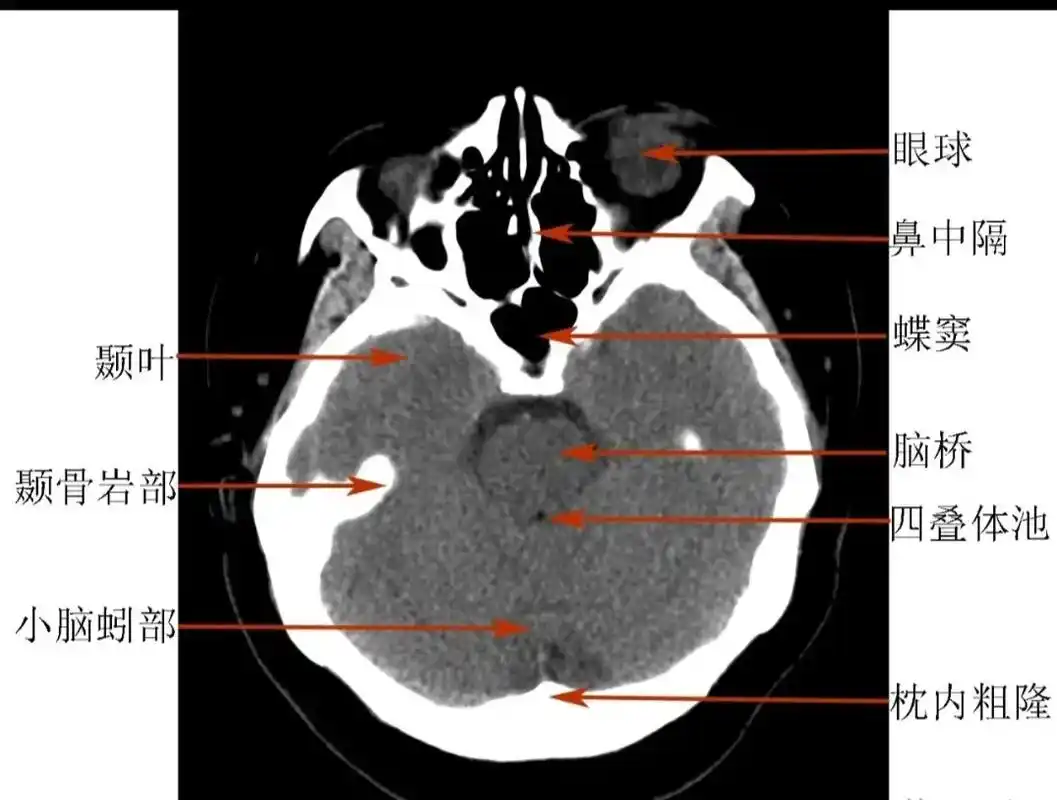

正常头颅ct.#愿所有人平安健康 #医学科普 #健康 - 抖音